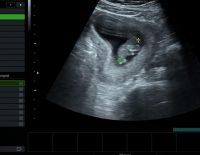

Siêu âm đầu dò âm đạo là kỹ thuật giúp kiểm tra và nhận định chính xác tình trạng sức khỏe sinh sản của nữ giới. Đồng thời có thể nhận biết được việc mang thai ngoài tử cung, các khối u bên trong. Vậy...